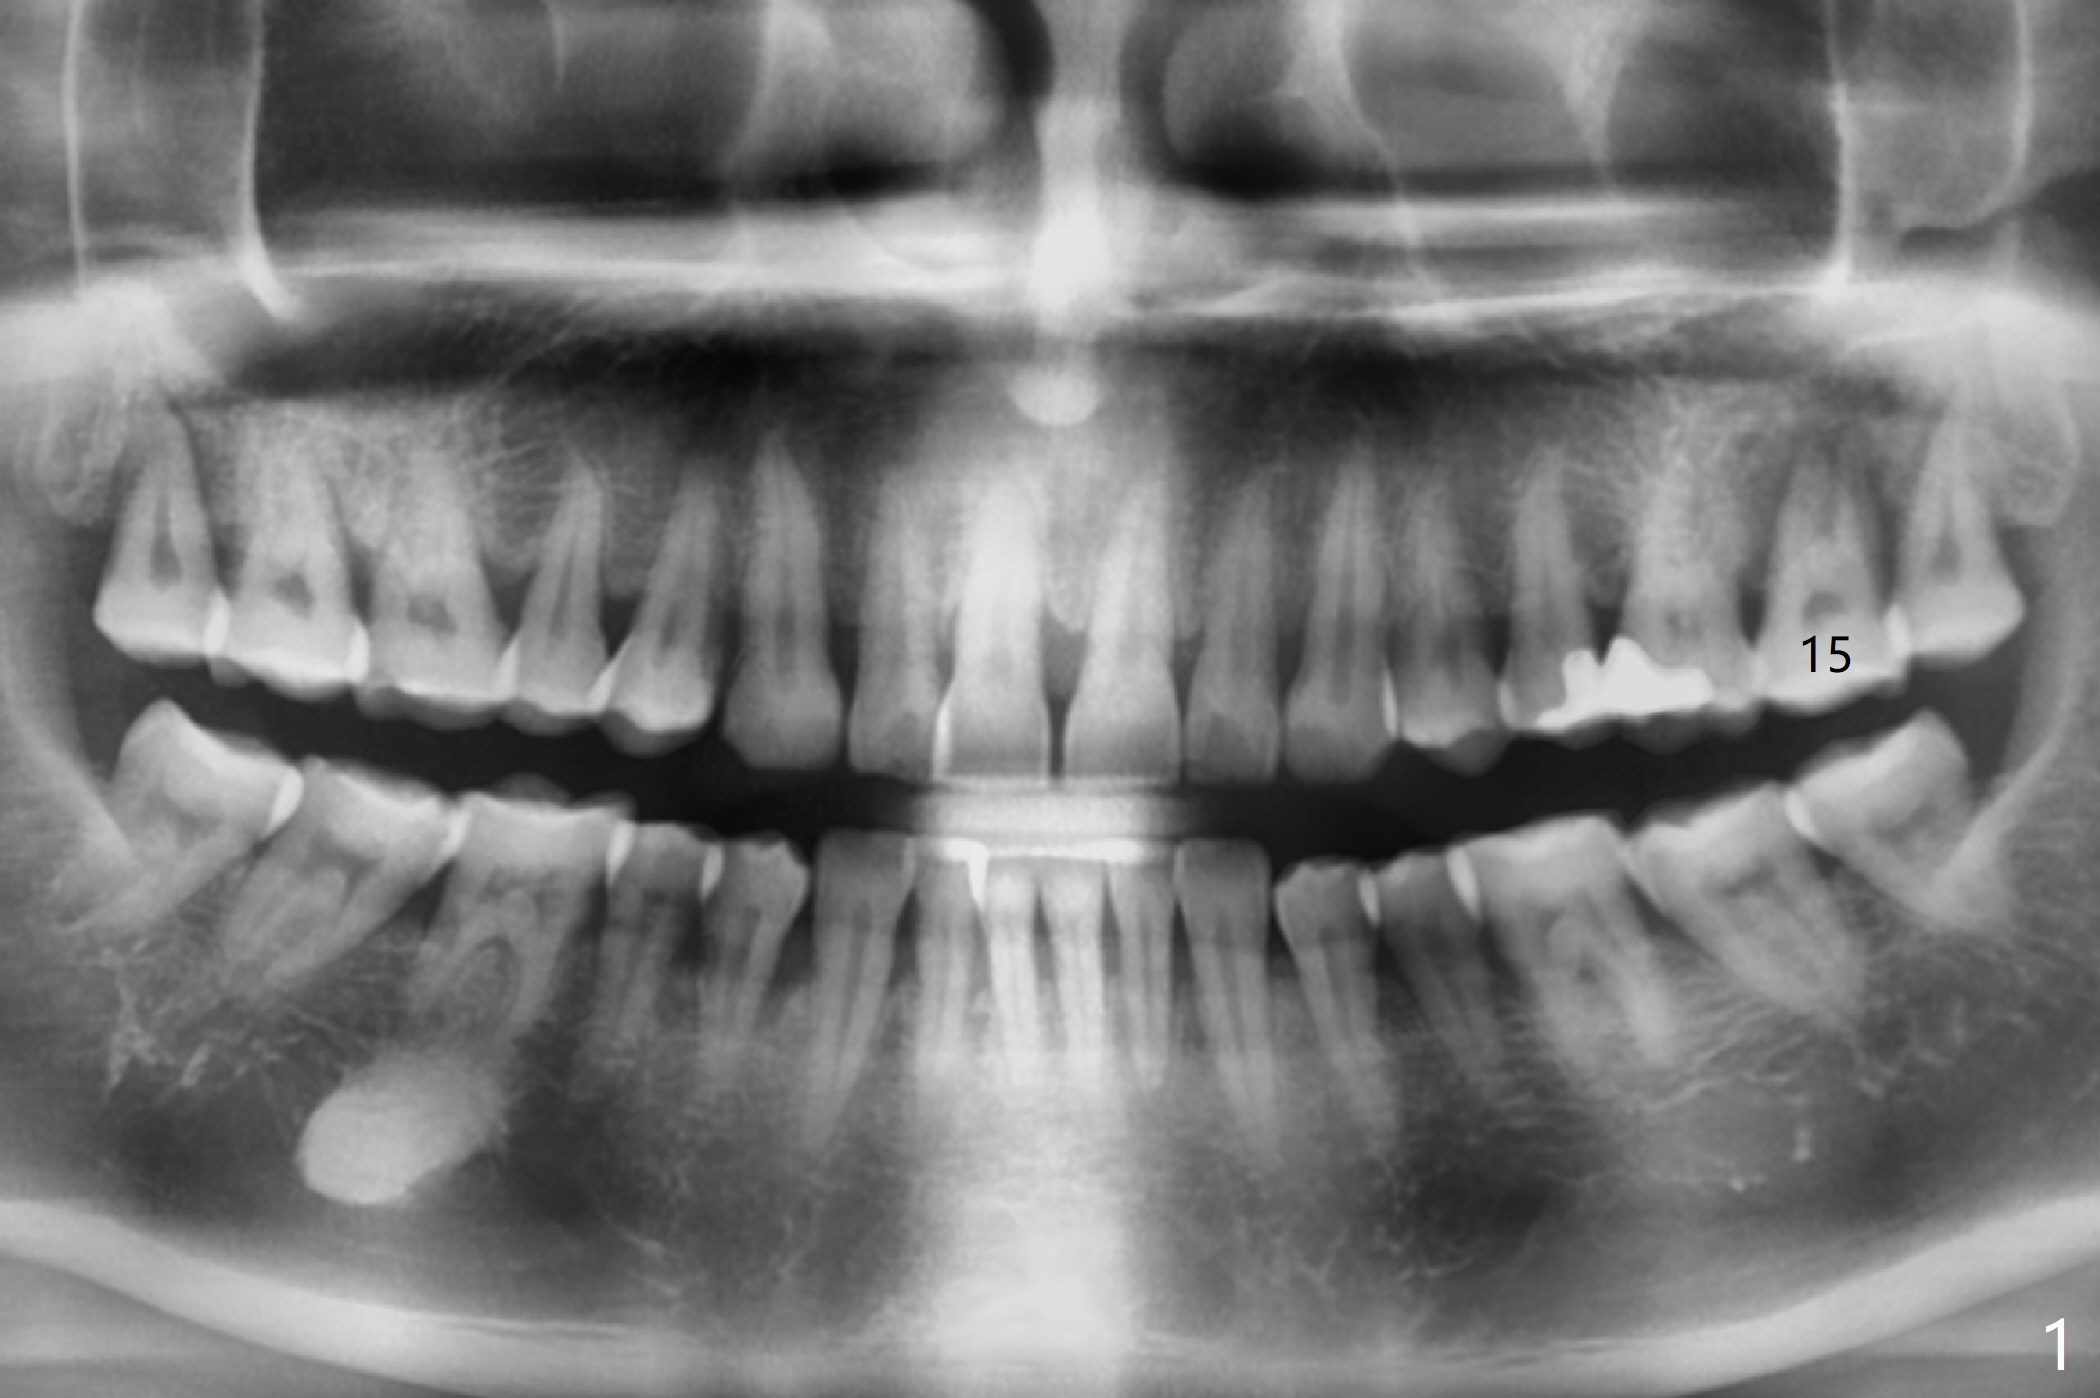

The 54-year-old woman (bruxer) agrees to have implant because of the loose tooth at #15 (Fig.1 (pan)). Since the left sinus membrane is thickened (Fig.2 *), an immediate implant will not be penetrated the sinus floor if primary stability is acceptable. If the sinus lift has to be done, PRF membrane/plug will be prepared. The large periradicular radiolucency is associated with the vertical palatal root fracture (Fig.3). A 5x8.5 mm implant is placed as buccal as possible with guide (Fig.4).